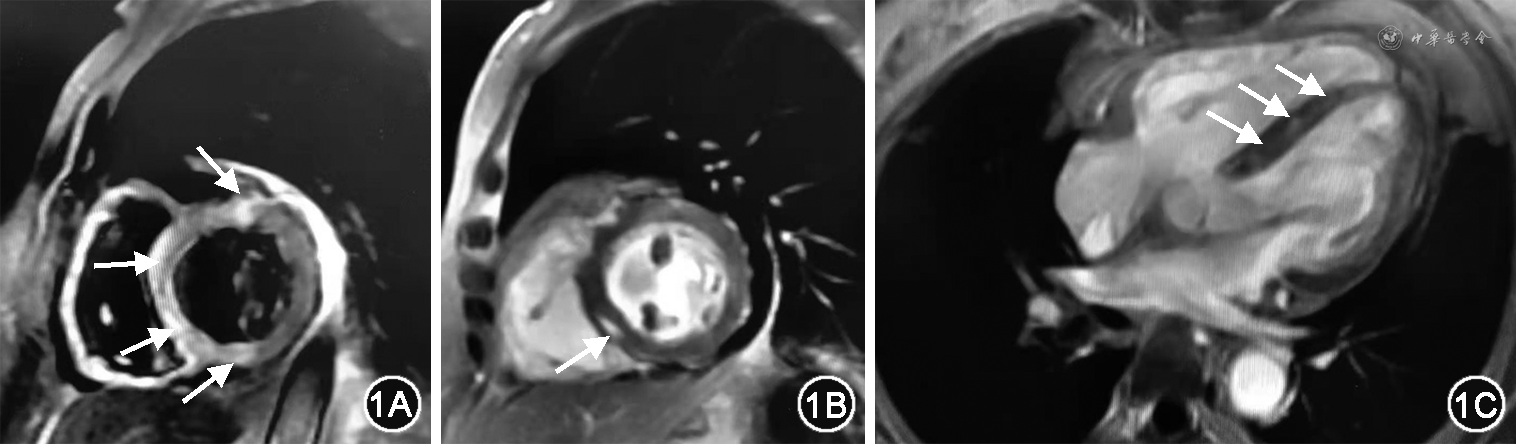

入院体格检查:体温36.2 ℃,心率103 次/min,呼吸20 次/min,血压100/69 mmHg(1 mmHg=0.133 kPa),神清,双侧眼睑下垂,左侧明显。双肺呼吸音清,未闻及干湿啰音。心律齐整,各瓣膜听诊区未闻及病理性杂音。腹部皮肤见手术瘢痕,双下肢无水肿,双下肢肌力4+级。实验室检查(2021-08-05):cTnI 2.200 mg/L,CK-MB 595 U/L,CK 20 313 U/L,NT-proBNP 6 580 ng/ml,ALT 950 U/L,AST 1 176 U/L,凝血功能、血沉、甲状腺功能、肝炎系列抗体未见明显异常,肌炎相关自身抗体(抗ANA抗体、抗ScL-70抗体、抗PM-ScL抗体、抗SSA抗体、抗SSB抗体)阴性,肌炎特异性自身抗体(抗Jo-1抗体)阴性。胸部CT:双肺散在渗出,心脏增大。肌电图:双侧尺神经、左侧腋神经、双侧副神经、双侧面神经低频(3 Hz)重复电刺激试验阴性,右侧腋神经低频(3 Hz)重复电刺激试验可疑阳性,左侧三角肌肌电图未见明显异常。超声心动图:心脏结构未见明显异常,室壁运动普遍减低,左心室射血分数(LVEF)34%。心脏磁共振(图1):左心室室间隔及毗邻前壁、下壁心肌组织T2压脂序列信号增强,考虑心肌水肿;左心室室间隔及毗邻前壁肌壁间见条片状及斑片状延迟强化。结合病史特点,且近期有PD-1抑制剂使用史,考虑“药物性心肌炎:免疫检查点抑制剂(immune checkpoint inhibitors,ICI)相关心肌炎可能性大”。